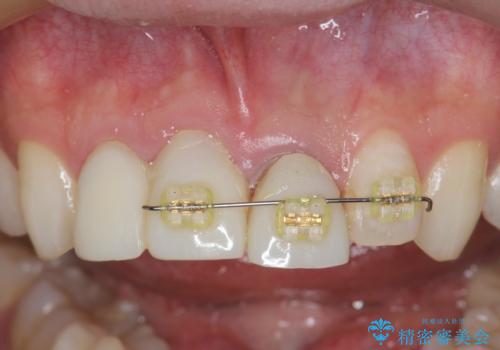

- 矯正装置

- 部分ワイヤー矯正

- 治療期間

- 10ヶ月

・歯肉縁下カリエス →部分矯正による歯の挺出・歯周外科